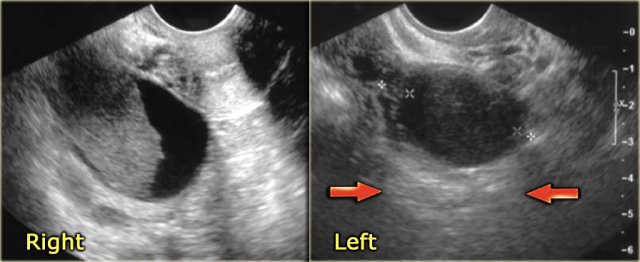

Hemorrhagic ovarian cyst in both right and left ovary Hemorrhagic ovarian cyst in both right and left ovary

The ultrasound images show the right and left ovary: on both sides there is what appears to be a solid lesion.

There is however good through transmission, which indicates that we are probably dealing with hemorrhagic cysts.

On Doppler US (not shown) there was no vascularity.

Continue with the MR examination.